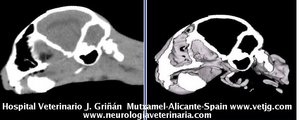

Mismo paciente: Correspondencias entre el corte sagital y el volumen, ambos reconstruidos a partir de imágenes TC (transversales) |